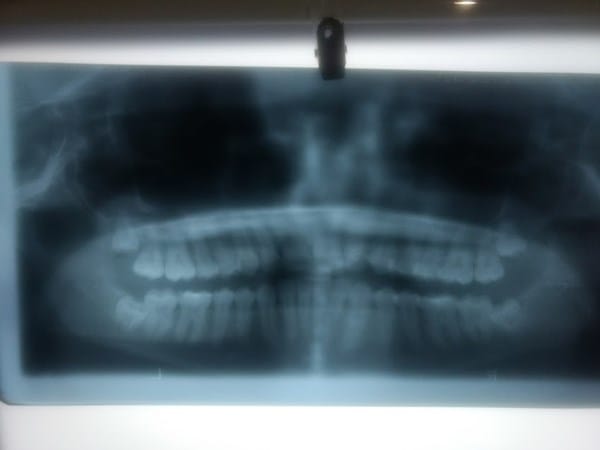

Tengo los segundo molares doblados, tengo que sacarme las muelas del juicio?

Esta panorámica la hizé a principio de este año, pero he notado las muelas se me han ido doblando, entonces quiero saber si obligatoriamente debo sacarme las muelas del juicio, ¿y si los segundos molares se podrían enderezar de nuevo? La muela izquierda estás más doblada que la derecha, pero las dos están ligeramente dobladas.

Me da miedo sacarme las muelas :(